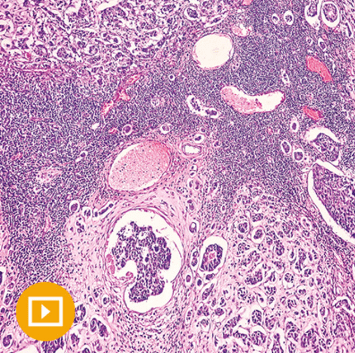

Breast Pathology — from Oakstone CME’s Masters of Pathology Series — outlines best practices for specimen handling and reporting, defined diagnostic criteria, improved recognition of less common diagnostic entities, and accurate interpretation of ancillary studies by using both routine microscopic examination and immunohistochemistry.

Papillary Lesions of the Breast – Edi Brogi, MD PhD

Papillary Lesions of the Breast – Microscopy Session – Edi Brogi, MD, PhD